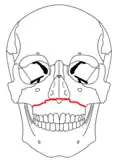

- The Le Fort I fracture (horizontal maxillary fracture) consists of a horizontal fracture through the pterygoid plates and maxillary bone between the hard palate and the orbits.[5] Involvement of the nasal aperture differentiates this fracture from the other two Le Forts.[5] Historically, this fracture was eponymically known as a Guérin fracture.[3]